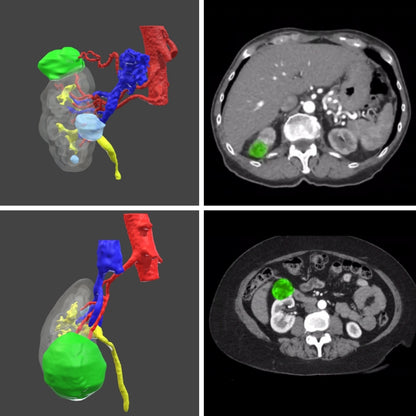

Surgical planning - Digital 3D model for urology

Surgical planning - digital model

Only for urology

Plan your next surgery with a 3D model of the patient's exact anatomy. This planning is done based on the CT scans.